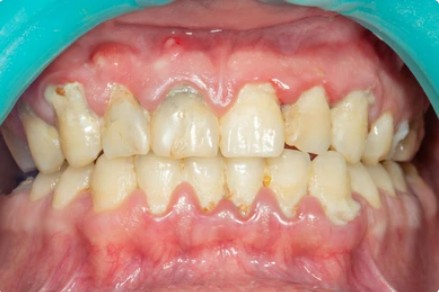

Co se stane, když se krvácení dásní neřeší

Pokud zánět přetrvává dlouhodobě, může přejít do hlubších struktur a vést k:

-

ústupu dásní,

vzniku parodontózy,

viklavosti zubů,

a postupně i k jejich ztrátě.